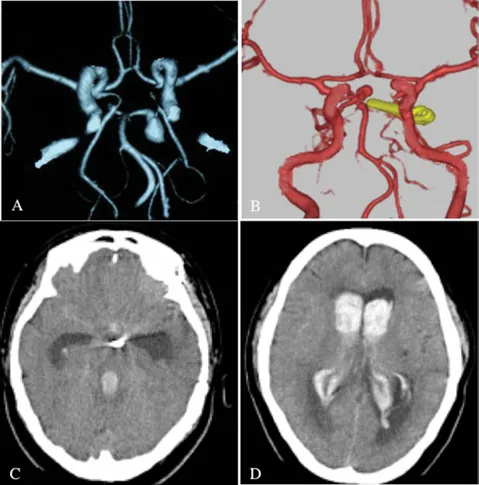

47岁男性患者陈先生在家中出现突发性剧烈头痛,随后迅速陷入昏...

当51岁王女士认为颅内动脉瘤已被彻底清除时,术后七年的突发状...